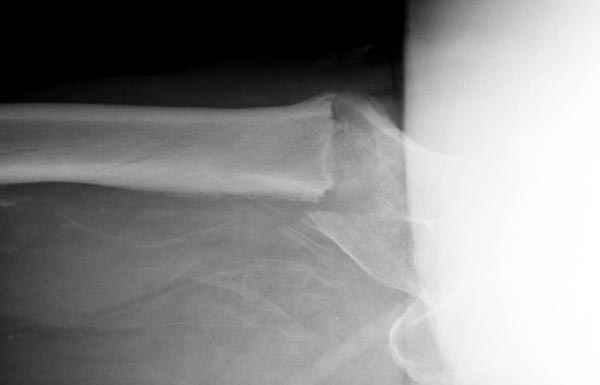

В общем, сделали. См. приложение.

Длина и из-за этого ось получились не совсем такие, как хотелось бы, все-таки срок после той операции уже 6 недель. Может быть, стоило провести дистракцию аппаратом неделю-другую. Заранее спасибо за комментарии и критику.

Точно. Плюс длина диафизарной части больше, чем у blade plate, и плечо рычага короче, чем у накостных фиксаторов.

Проксимальный фрагмент весь разрушен, и эти два фиксатора нужно было как-то соединять, винты через пластину чтобы прошли через отверстия в стержне. Это было бы и труднее, и устойчивость все-таки меньше, чем у гвоздя проксимального типа.